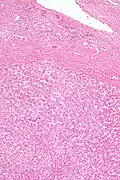

Pathologic diagnosis

Hepatic adenomas are, typically, well-circumscribed nodules that consist of sheets of hepatocytes with a bubbly vacuolated cytoplasm. The hepatocytes are on a regular reticulin scaffold and less or equal to three cell thick.

The histologic diagnosis of hepatic adenomas can be aided by reticulin staining. In hepatic adenomas, the reticulin scaffold is preserved and hepatocytes do not form layers of four or more hepatocytes, as is seen in hepatocellular carcinoma.

Cells resemble normal hepatocytes and are traversed by blood vessels but lack portal tracts or central veins.

Micrograph of hepatic adenoma. H&E stain -